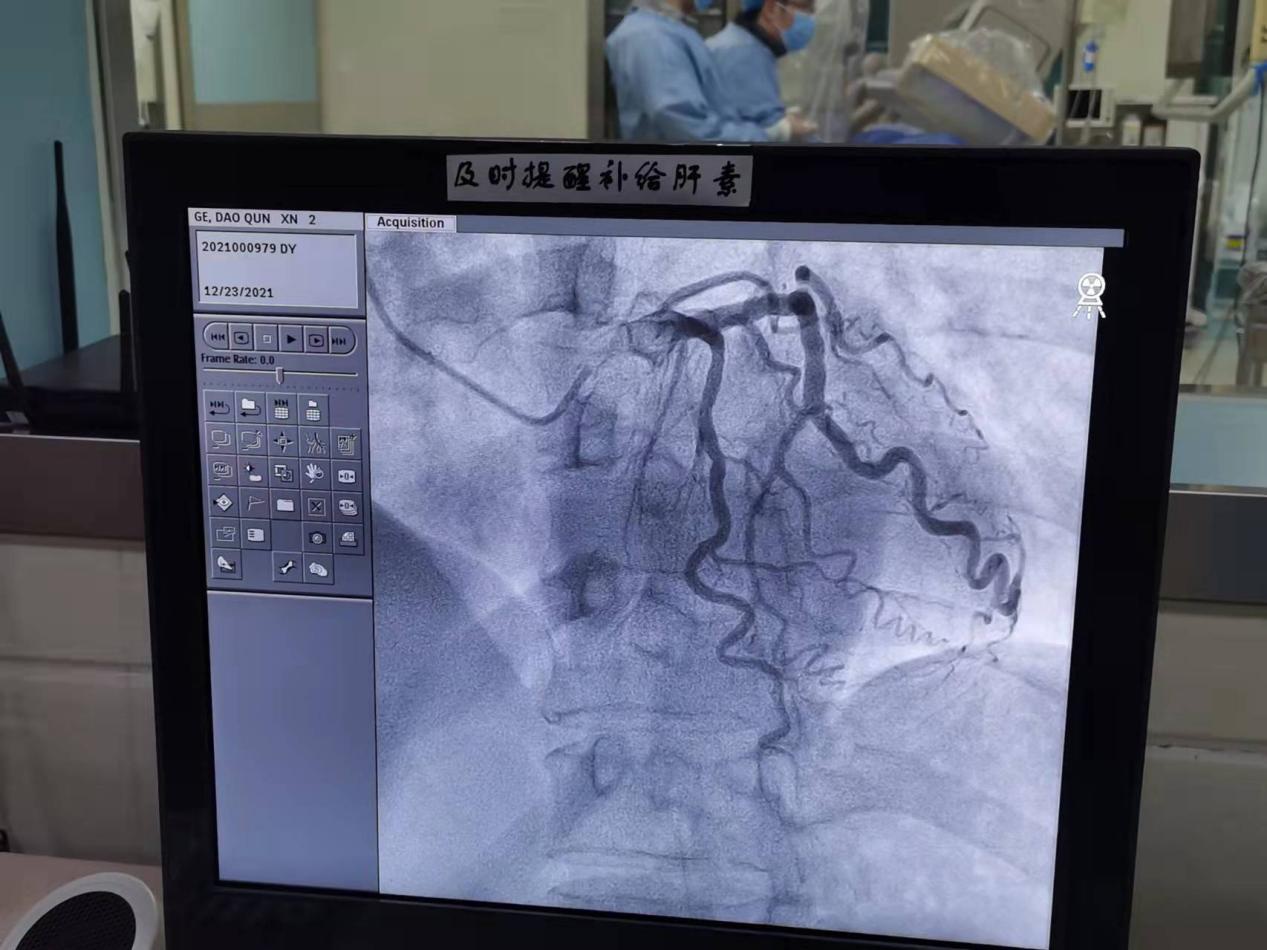

安医大一附院东城院区(肥东县人民医院)导管室,一台心脏冠状动脉介入手术正在开展。在医学影像技术的支持下,患者的血管影像直观显示在屏幕上。监控室里,安医大一附院东城院区院长、心血管内科专家张勇实时关注着手术进展。

张勇在监控室关注手术实时医学影像(总台央广记者谭瑱 摄)

穿刺患者手臂上的桡动脉,置入导管,导入导丝,手术进展顺利。随后,导管内被注入造影剂,犹如开了“探照灯”一样,冠状动脉血管堵塞情况瞬时显示在屏幕之上。在院区心血管内科副主任侯杰的精准操纵下,头发丝粗细的金属导丝顺着导管被送往心脏的冠状动脉血管,为后续的血管疏通工作建好了通路。

造影剂显影(总台央广记者谭瑱 摄)